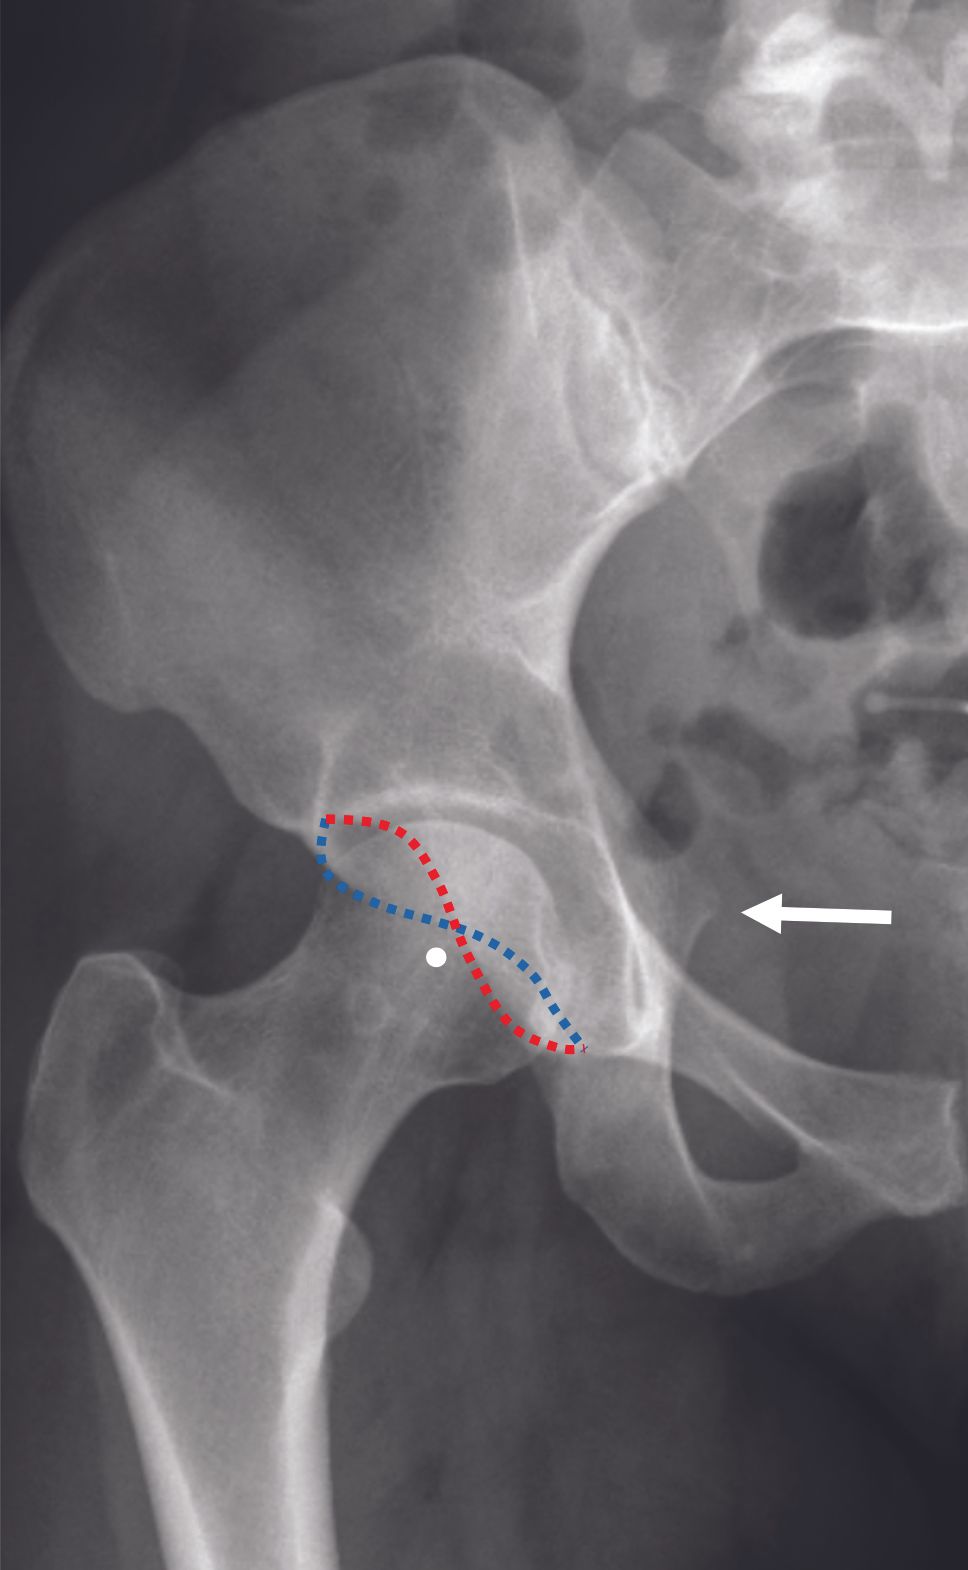

The orientation of the acetabulum is important to assess, as it can also be the source of a pincer-type FAI if the acetabulum is retroverted (Figure 4).

The retroversion of the acetabulum may be focal (<30%) or global (>30%) depending on the crossing sign size. Posterior wall sign (posterior wall medial to the center of the femoral head), and ischiatic spine sign (visible on front pelvic film beyond the iliopubic line) are the two other signs for acetabulum retroversion. The filling of the cervico-cephalic junction can cause a cam effect (Figure 5), sometimes with a pistol grip appearance. The cam effect can be quantified using the alpha angle measured on the axial radiograph.